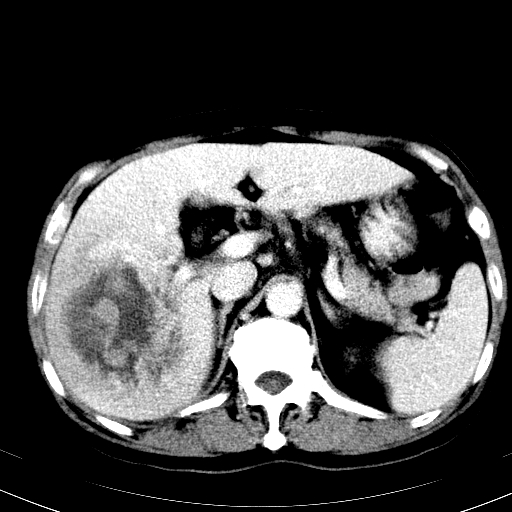

以下是引用卜一在2008-6-23 15:38:00的发言:[br]本例延时期的图象未扫完,单纯平扫 动脉期及门脉期特征分析:平扫低密度较大肿块,内见不规则出血灶,界限清楚。动脉期边缘结节样强化,门脉期病灶边缘进一步强化并范围明显缩小。因此考虑:血管瘤伴出血!

以下是引用深泽交通医院在2008-6-23 16:40:00的发言:[br]考虑肝癌伴出血.诊断依据:平扫瘤壁结节密度低于肝实质,动脉期壁结节明显强化,门脉期略低于肝实质密度[br]病灶有明显的假包膜,